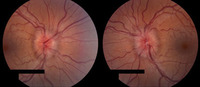

Hipertensão intracraniana idiopática

Estágio 3 da escala de Frisén

Do acervo pessoal do Dr. M. Wall; usado com permissão